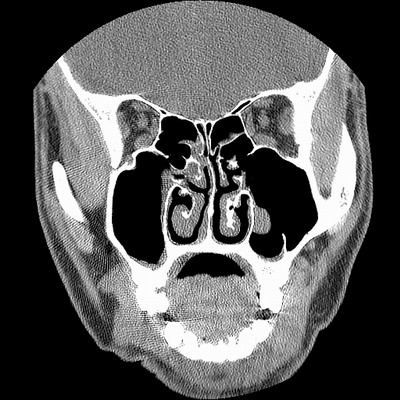

男,38岁,鼻塞、头痛2个月,要求鼻窦ct检查。

右侧上颌窦、蝶窦、筛窦、额窦及左侧上颌窦慢性炎症。

右侧鼻中隔左偏,右侧上颌窦、筛窦、额窦慢性炎性病变。右侧上颌窦开口粘膜增厚。

1)副鼻窦炎。2)右侧中鼻道及总鼻道粘膜息肉样变。3)双侧中下鼻甲肥大。4)鼻中隔轻度左突偏曲。